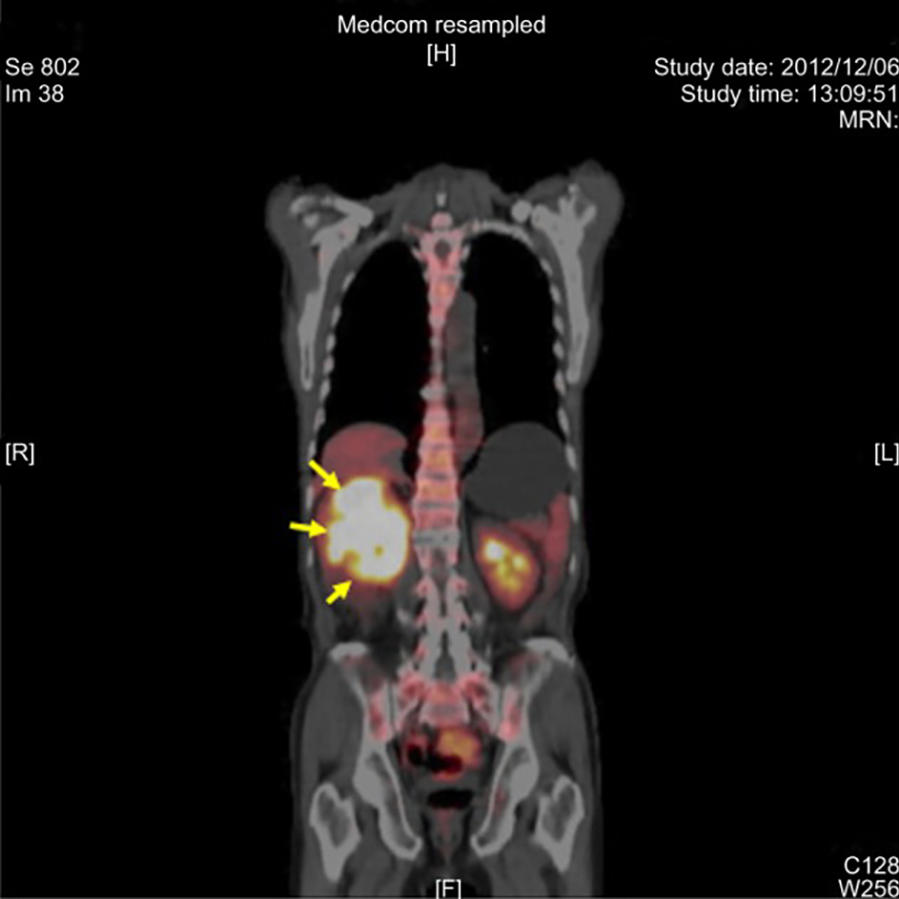

Medical PET scan showing a tumor in the right kidney, highlighted with yellow arrows pointing to the bright yellow-white areas indicating areas of increased metabolic activity typical of cancerous tissue.

PET scan of a tumor in the right kidney (arrows).

Credit: Onco Targets Ther Feb 2014. doi: 10.2147/OTT.S58089. CC-BY 3.0